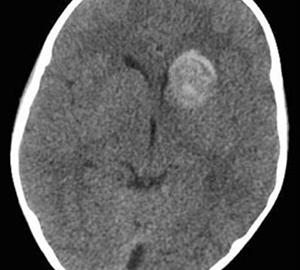

Motivo de consulta: cuadro progresivo de desorientación, apatía, bradipsiquia y disartria, seguido de un episodio de pérdida de conocimiento.